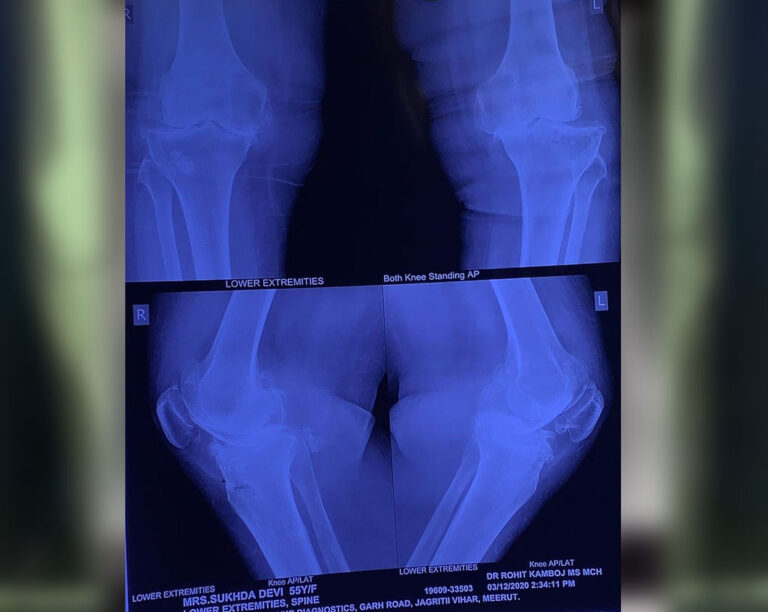

Total Knee Replacement

Name: Sudha Devi

Date of Operation: Dec 2020

Age: 59 Years

Before Surgery